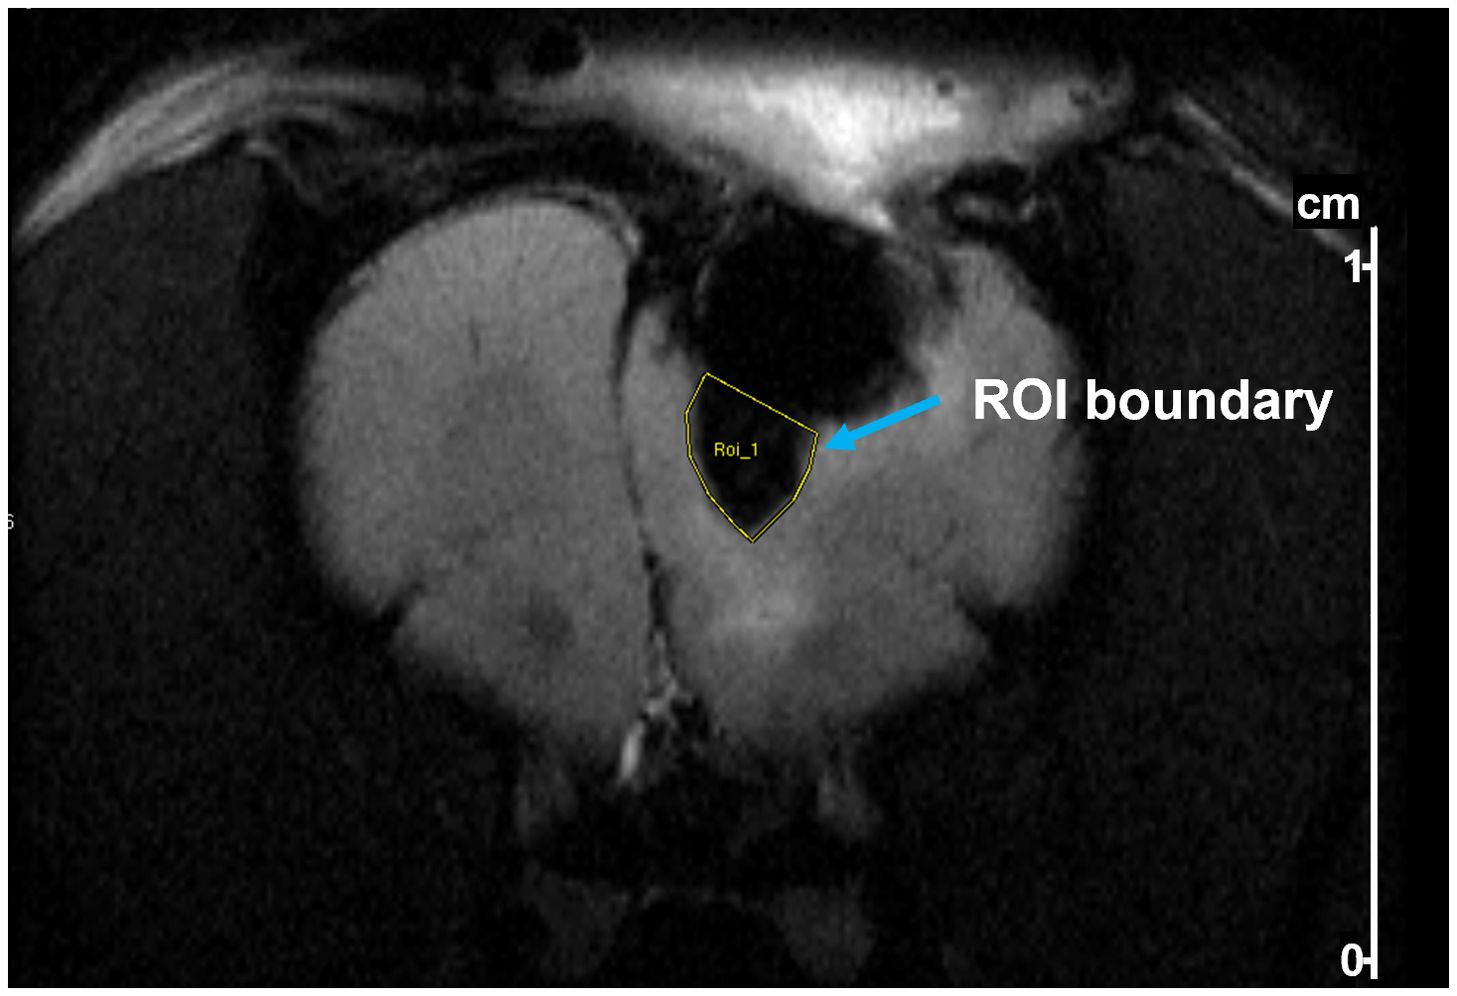

Perfusion of SPIONS on MRI images were measured using the region of interest (ROI) tool embedded in ParaVision 5.1 software (Bruker) to manually delineate a perfusion area by drawing a boundary defined by the high contrast between SPION-labeled perfusion and surrounding tissue. The boundary was guided by clear signal intensity differences on the MRI images, particularly distinguishing the SPION-enhanced regions. The software computed the ROI area and pixel count to quantify perfusion distribution.

SPION perfusion was calculated from MRI images using the ParaVision software tool to draw a polygon boundary defined by the high contrast between SPION-labeled perfusion and surrounding tissue (an example is shown in Figure 5). For Rat 1, the area of SPION perfusion increased by 0.02 cm² over 3 days, while for Rat 2, it increased by 0.06 cm² over 7 days (Table 1).

Figure 5. Example of delineation of a region of interest (ROI) in a T2-weighted MR image of a rat after tumor resection and pump implantation. The ROI (yellow outline) was drawn to quantify SPION perfusion below the pump. Delineation was performed using Bruker ParaVision software based on contrast between iron oxide-labeled regions and surrounding brain tissue.